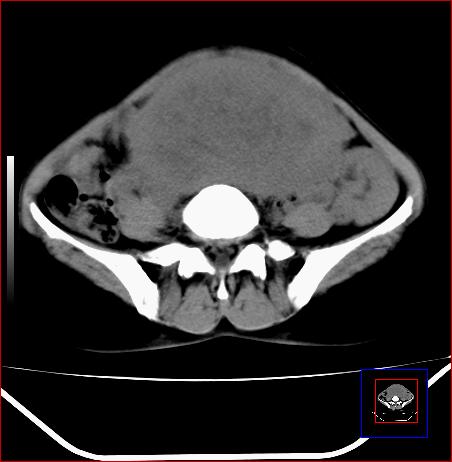

标题: CT15141:子宫肌瘤还是卵巢肿瘤 [打印本页]

标题: CT15141:子宫肌瘤还是卵巢肿瘤

腹部包块1年余,近两月明显增大,月经量多

病灶呈实性包块,边界清晰,似与子宫分界不清,考虑:子宫肌瘤

子宫体积增大,内密度不均匀。边缘清晰。考虑子宫肌瘤。

病灶呈实性包块,边界清晰,似与子宫分界不清,考虑:子宫肌瘤可能性大。其他待排

子宫体积增大,内密度不均匀。边缘清晰。考虑子宫肌瘤可能性大。